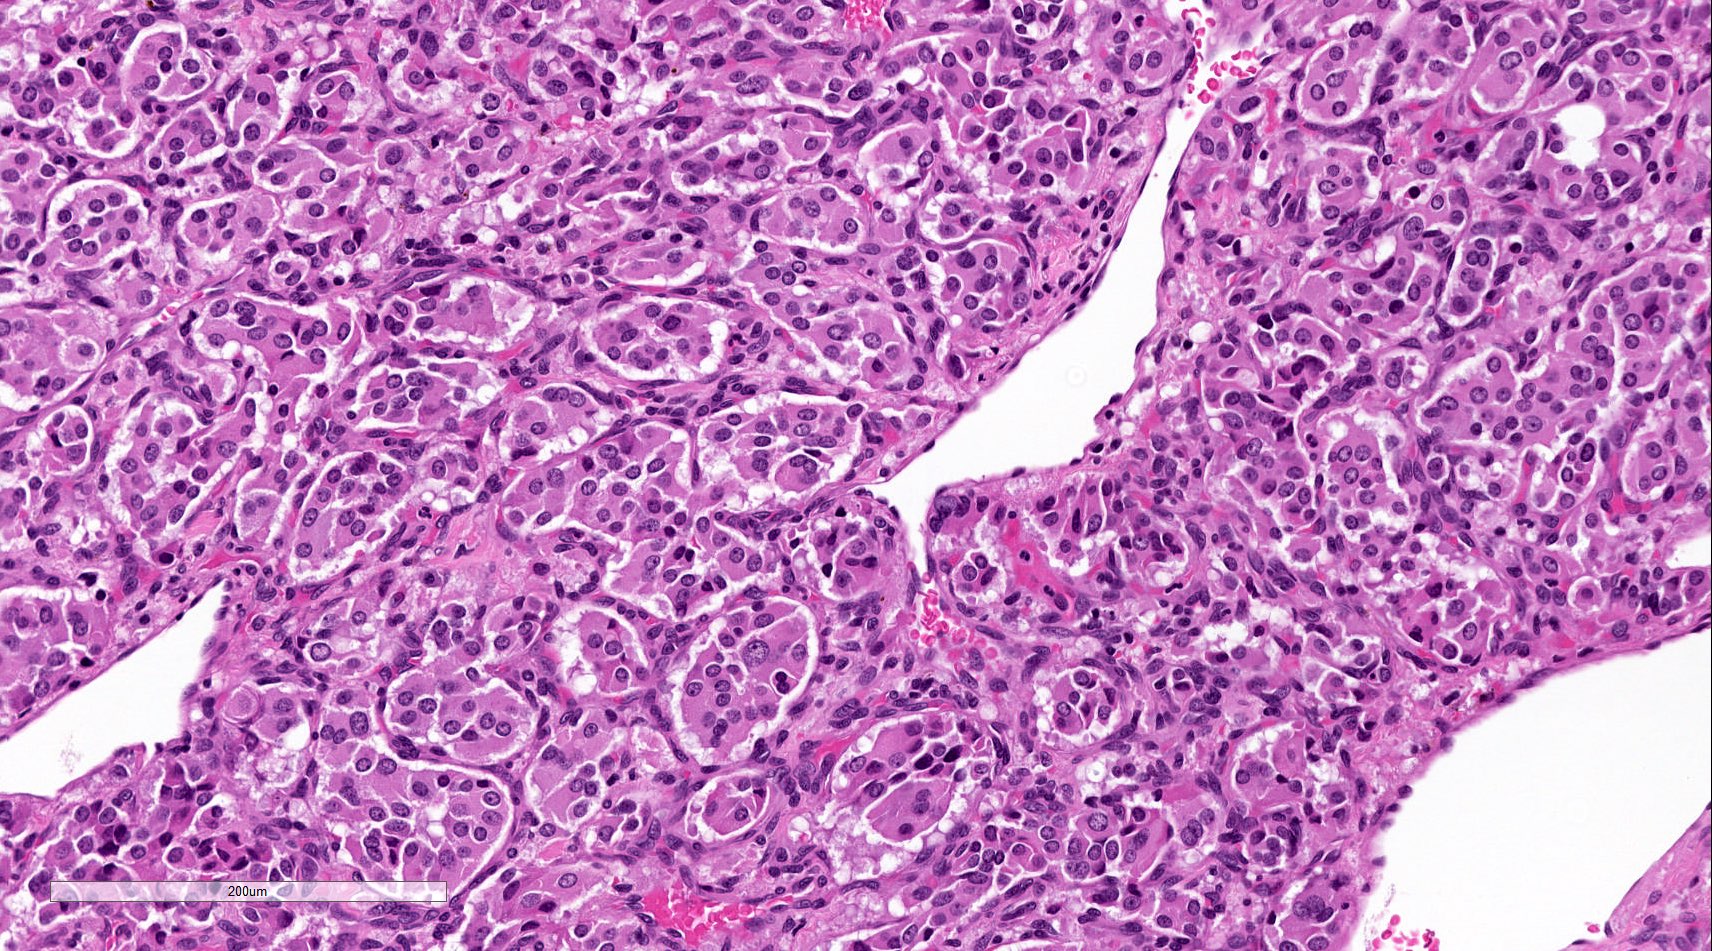

Microscopic (histologic) description

- Prevailing histologic pattern: epithelioid chief cells arranged in distinctive clusters / nests (zellballen pattern), separated by prominent fibrovascular stroma (J Clin Med 2018;7:280)

- Trabecular pattern: ribbons or cords of epithelioid cells divided by fibrous bands

- Other patterns: pseudorosette, angioma-like, spindled and sclerosing

- Chief cells: round, oval to polygonal cells with abundant granular basophilic, eosinophilic or amphophilic cytoplasm (Surg Pathol Clin 2019;12:951)

- Intracytoplasmic hyaline globules may be present in sympathoadrenal paragangliomas

- Giant multinucleated cells and bizarre cells can be present (Srp Arh Celok Lek 2002;130:7)

- Rarely, elongated and spindle shaped cells with a sarcomatoid appearance may be found

- Scattered ganglion cells can be seen

- May have nuclear atypia

- May have dysmorphic vessels, melanin-like pigment (neuromelanin) (pigmented paraganglioma), amyloid, abundant stroma and osseous metaplasia (Diagn Pathol 2012;7:77, Hum Pathol 1992;23:33)

- No or rare mitotic figures except in highly aggressive rapidly proliferating lesions

- May have focal chronic inflammatory infiltrate

- Necrosis is unusual except in patients who have undergone preoperative tumor embolization

Microscopic (histologic) images

Contributed by Luvy Delfin, M.D. and Sylvia L. Asa, M.D., Ph.D.